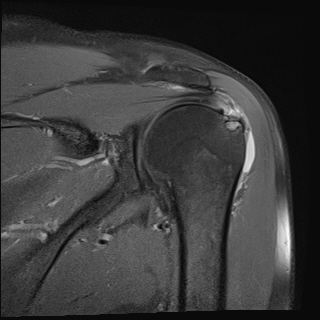

ÀÚ±â°ø¸í°Ë»ç

±Ø»ó°Ç ÆÄ¿­, Á¡¾×³¶¿°, °ßºÀÇÏ °ñ±Ø